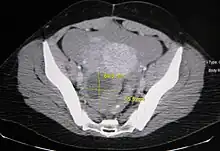

Ovarian cysts are usually diagnosed by ultrasound, CT scan, or MRI, and correlated with clinical presentation and endocrinologic tests as appropriate.[10]

Ultrasound

Follow-up imaging in women of reproductive age for incidentally discovered simple cysts on ultrasound is not needed until 5 cm, as these are usually normal ovarian follicles. Simple cysts 5 to 7 cm in premenopausal females should be followed yearly. Simple cysts larger than 7 cm require further imaging with MRI or surgical assessment. Because they are large, they cannot be reliably assessed by ultrasound alone; it can be difficult to see posterior wall soft tissue nodularity or thickened septation due to limited ultrasound beam penetrance at this size and depth. For the corpus luteum, a dominant ovulating follicle that typically appears as a cyst with circumferentially thickened walls and crenulated inner margins, follow up is not needed if the cyst is less than 3 cm in diameter. In postmenopausal patients, any simple cyst greater than 1 cm but less than 7 cm needs yearly follow-up, while those greater than 7 cm need MRI or surgical evaluation, similar to reproductive age females.[11]

For incidentally discovered dermoids, diagnosed on ultrasound by their pathognomonic echogenic fat, either surgical removal or yearly follow up is indicated, regardless of patient age. For peritoneal inclusion cysts, which have a crumpled tissue-paper appearance and tend to follow the contour of adjacent organs, follow up is based on clinical history. Hydrosalpinx, or fallopian tube dilation, can be mistaken for an ovarian cyst due to its anechoic appearance. Follow-up for this is also based on clinical presentation.[11]

For multiloculate cysts with thin septation less than 3 mm, surgical evaluation is recommended. The presence of multiloculation suggests a neoplasm, although the thin septation implies that the neoplasm is benign. For any thickened septation, nodularity, vascular flow on color doppler, or growth over several ultrasounds, surgical removal may be considered due to concern of cancer.[11]